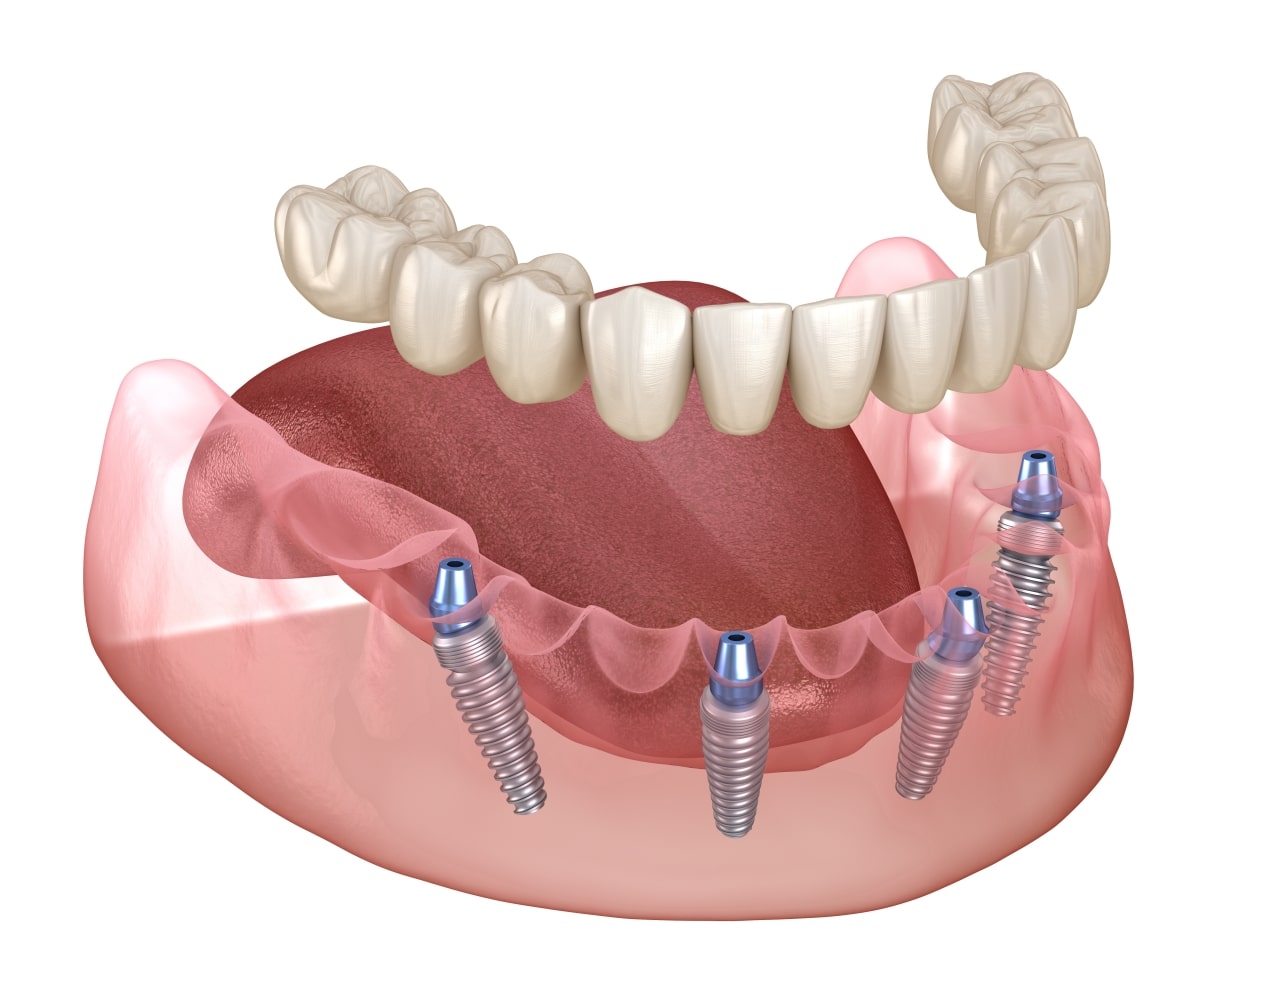

All-on-4, cunoscuta si sub denumirea Fast & Fixed, este o procedura chirurgicala de reabilitare totala.

Conceptul de tratament All-on-4/6 este o procedură chirurgicala si protetică (adică înlocuirea dinților lipsă) care asigură o înlocuire permanentă a acestora.

Adesea, pierderea dinților este însoțită de pierderea osului maxilar, ceea ce pune problema reconstrucției osului maxilar care necesită grefarea osoasă . Tehnica All-on-4 profită de osul dens care rămâne în partea din față a maxilarelor și prin plasarea celor două implanturi posterioare în unghi pentru a evita sinusul – cavități în maxilarul superior – și a canalul mandibular în maxilarul inferior -;

In cazul inserarii a 4 implanturi se pot realiza lucrari protetice definitive cu dinți din rășină acrilică (sau alte materiale cu greutate redusa) peste o bara de titan.

In cazul in care oferta osoasa este suficienta pe zonele laterale, se pot insera 6 implanturi si se pot realiza lucrari protetice definitive mai estetice si cu fiabilitate mai mare (metalo – ceramica sau zirconiu);• In ce consta aceasta procedura?

– inserarea a 4 sau 6 (sau 8 in unele cazuri) implanturi/arcada – in functie de lucrarea protetica pe care si-o doreste pacientul.